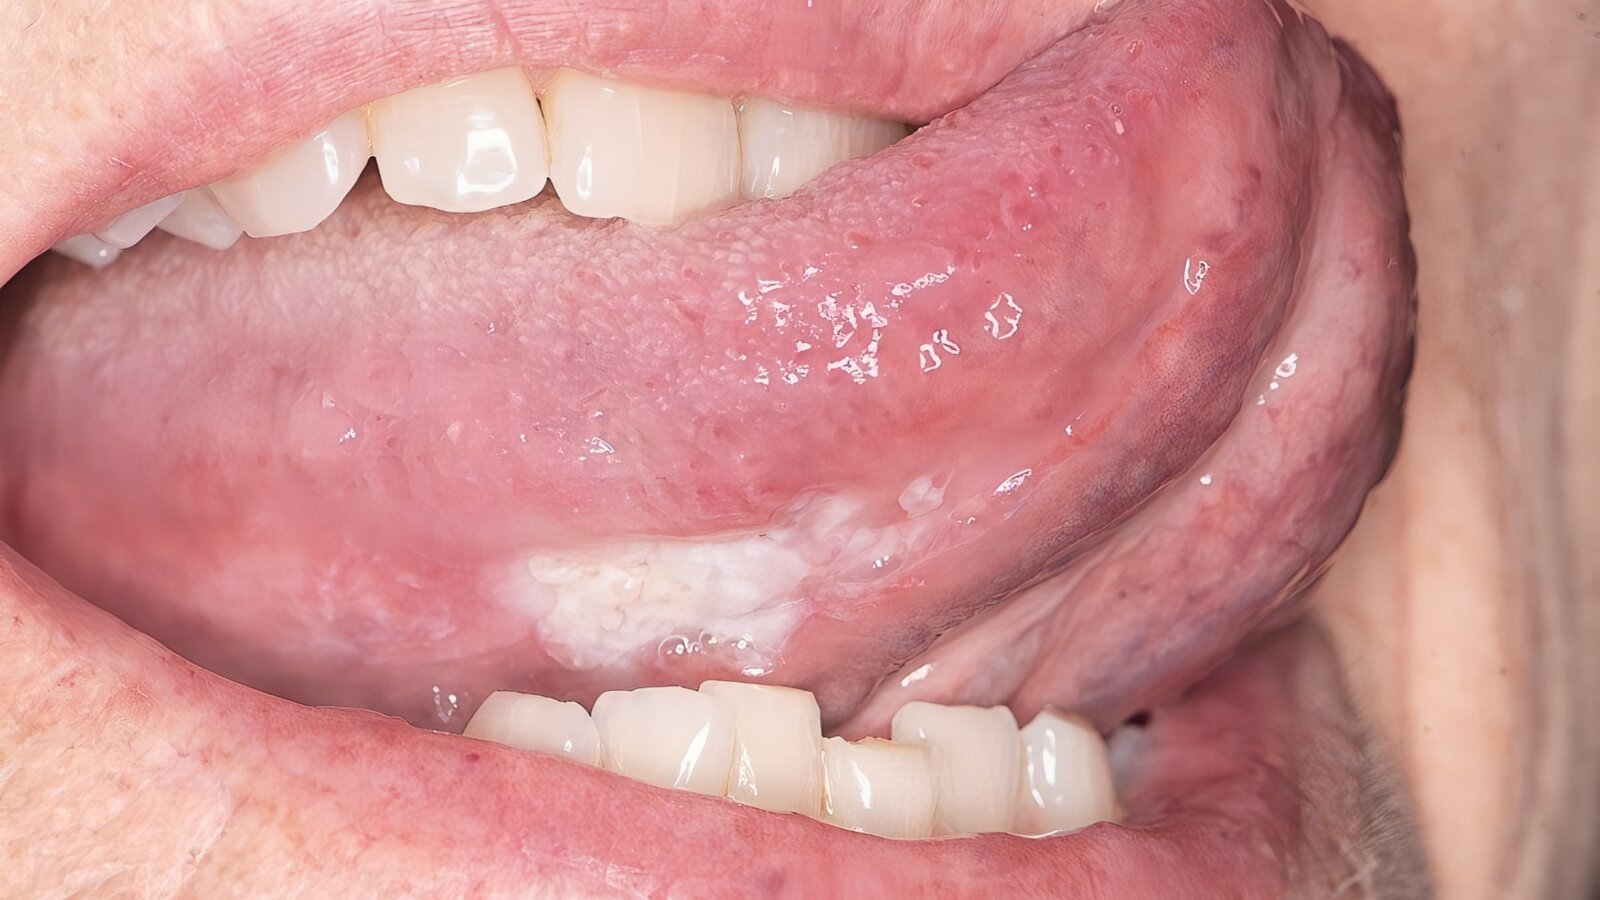

La leucoplasia, lesión precancerosa que se caracteriza por una placa blanca que no se desprende al raspado, podría ser tratada con este compuesto. Foto: UCLA

Catorce meses después de la primera inyección, el 85% de los pacientes había experimentado una disminución del tamaño de la lesión. De media, el área de la lesión se redujo un 60%, y 19 pacientes experimentaron reducciones superiores al 50%. Además, no se produjeron toxicidades limitantes de la dosis con el tratamiento, pues los acontecimientos adversos más frecuentes fueron fatiga, diarrea y erupción cutánea.